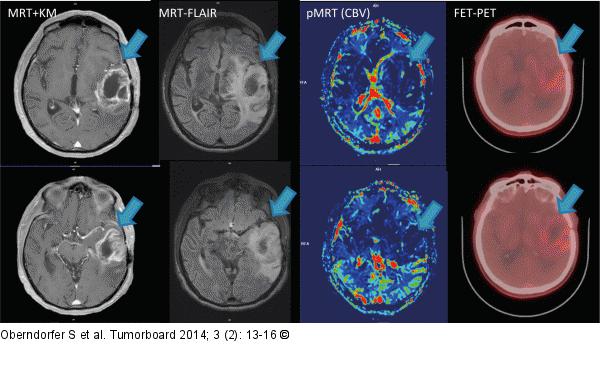

Abbildung 3: Glioblastom Follow-up-Imaging vom Februar 2014: MRT + KM, MRT FLAIR und pMRT, sowie FET-PET zeigen deutliche Hinweise für „Pseudoprogression“. Deutlich ausgeprägte KM-Aufnahme (MRT + KM), verminderte Perfusion in der pMRT und herabgesetzte Traceraufnahme im FET-PET im Vergleich zum Vorbefund (Tumorbereich mit Pfeil markiert) |

Follow-up-Imaging vom Februar 2014: MRT + KM, MRT FLAIR und pMRT, sowie FET-PET zeigen deutliche Hinweise für „Pseudoprogression“. Deutlich ausgeprägte KM-Aufnahme (MRT + KM), verminderte Perfusion in der pMRT und herabgesetzte Traceraufnahme im FET-PET im Vergleich zum Vorbefund (Tumorbereich mit Pfeil markiert) |